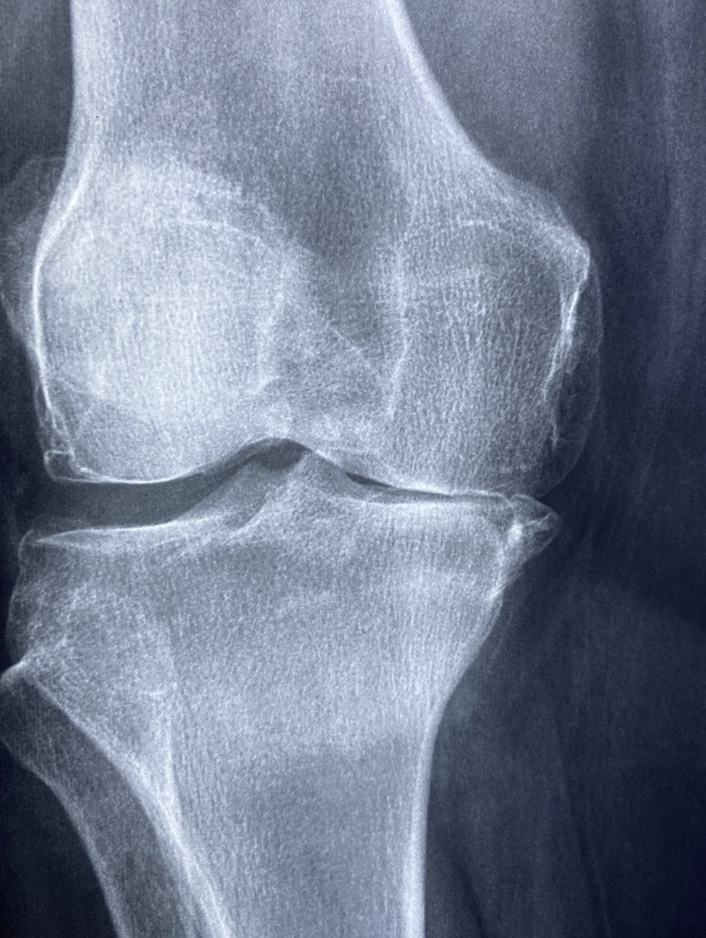

① 퇴행성 관절염 (골관절염, Osteoarthritis)

퇴행성 관절염은 나이가 들면서 연골이 닳아 없어지는 질환으로, 무릎, 손가락, 척추 등에 주로 발생합니다. 원인으로는 노화, 비만, 과도한 운동, 유전적 요인 등이 있으며, 치료법으로는 약물 치료, 물리치료, 생활습관 개선 등이 있습니다.